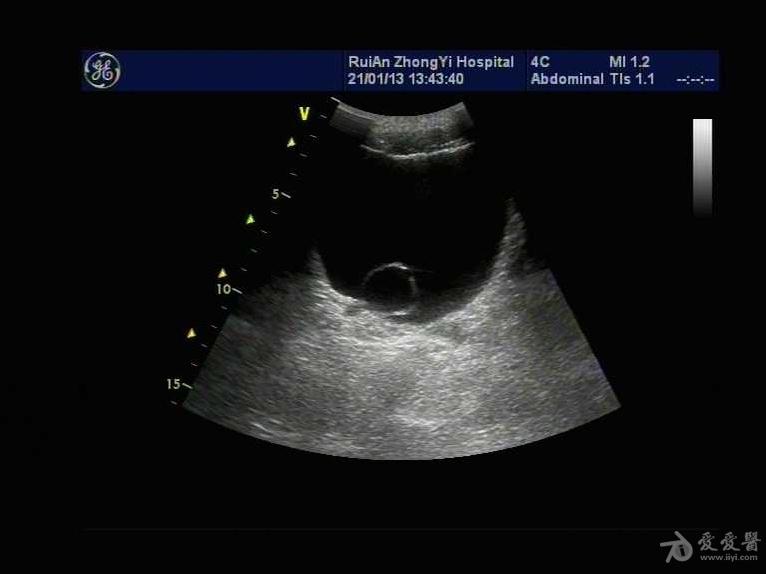

肾盂旁囊肿超声

肾盂旁囊肿超声,肾盂旁囊肿

肾盂旁囊肿